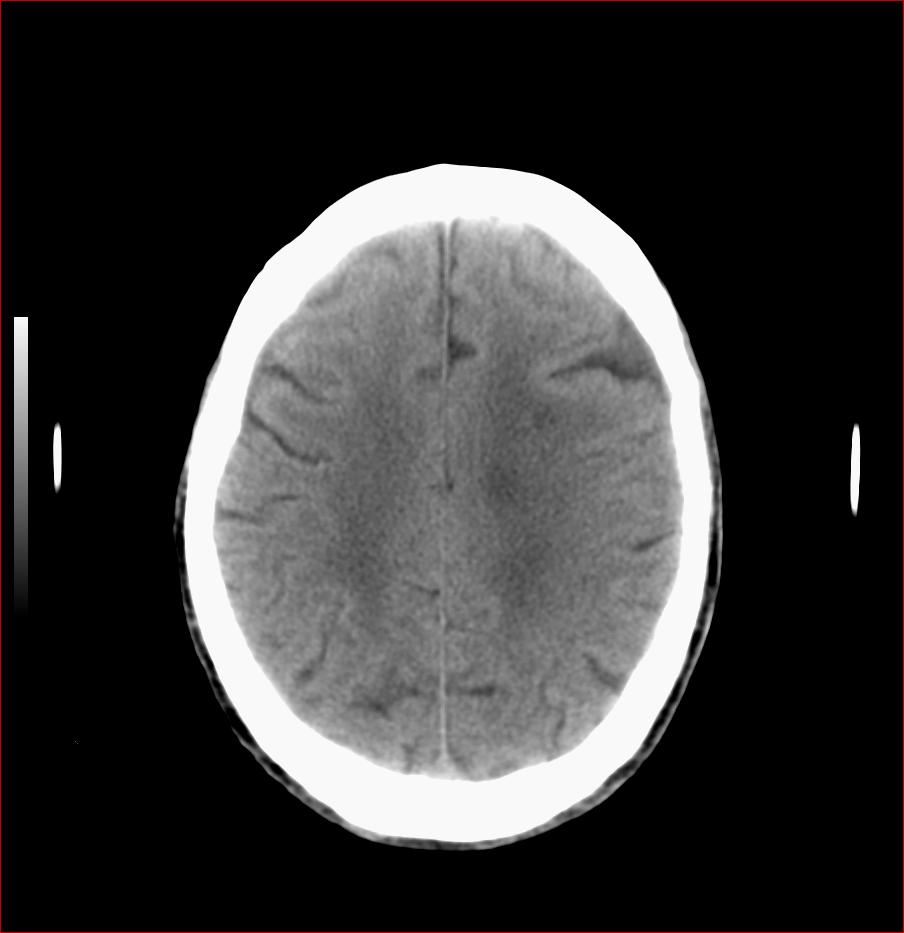

男,84岁,左下肢无力伴口角歪斜1天,血压160/80。请问一下双侧基底节区是脑梗塞吗?

双侧基底节腔梗,脑痿缩

基底节区脑梗塞,脑萎缩,左侧小脑脑梗塞

多发脑梗塞,白质疏松,脑萎缩

右侧基底节区斑片状低密度影,边缘模糊,结合临床考虑:1.右侧基底节区脑梗塞;2.老年性脑改变。

双侧基底节多发腔梗,皮层下动脉硬化性脑病

1.两侧基底节区及右顶深部脑梗塞。2.右侧外囊区脑软化灶。3.脑萎缩。4.脑白质脱髓鞘改变。

1.双基底节区及双顶深部脑梗塞;2.右外囊区软化灶;3.皮层下动脉硬化性脑病.